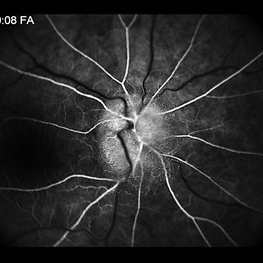

Drusen

Male patient 27-years-old, with complaint of low vision in both eyes. The fundoscopic evaluationfound the presence of drusen topography in the posterior pole with foveal. Fluorescein angiography shows the typical pattern of hyperfluorescence of drusen in the first minute of angiography.

Photographer: JEFFERSON R SOUSA - Study Center and Ophthalmological Research Dr. Andre M V Gomes, Institute Dr. Suel Abujamra São Paulo-Brazil

Imaging device: Topcon TRC-50 DX, Imaginet 5.0, angle de 50 graus. Flash 150.

Condition/keywords: colloidal drusen, drusen